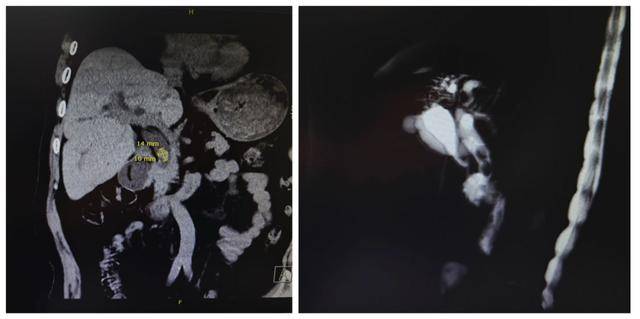

主治医生刘春,科室同事都亲切地称他为“春哥”。面对高龄、病情复杂且危重的王奶奶,刘春医生没有回避,他将家属请到办公室,在灯光下指着影像片子,用最朴实的语言,将那个堵塞的结石、扩张的胆管以及已经“罢工”的左半肝指给家属看,并详细解释了为何必须进行那套复杂的“组合拳”手术。

首先通过影像学检查明确结石位置、胆管扩张程度及左半肝萎缩情况。